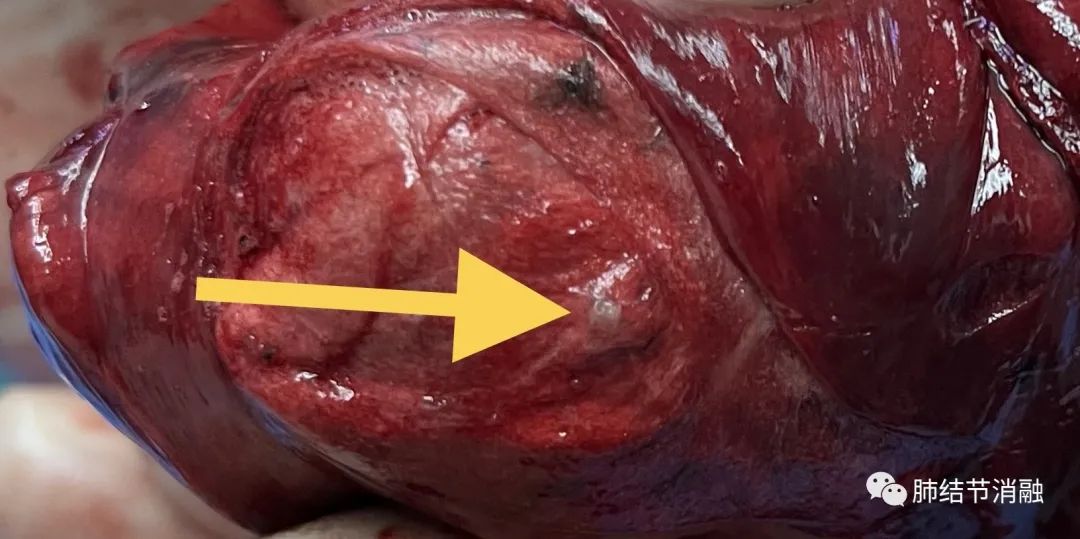

磁导航定位次要病灶2,这个病灶难度最大,就在气管边上,需要打隧道才能达到,我们在接近结节附近染色。

次要病灶2染色区域,气管边上

次要病灶2 3毫米结节